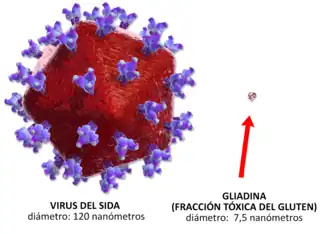

La celiaquia se desencadena en personas genéticamente predispuestas como consecuencia de la interacción entre el gluten y otros factores ambientales exógenos, y la respuesta inmunitaria. Se induce por la ingesta de gluten, a través de una fracción denominada gliadina.[27]

La gliadina es la fracción soluble en alcohol del gluten. Es una proteína rica en residuos de glutamina y prolina, y contiene la mayor parte de los productos tóxicos. Las moléculas de gliadina no digeridas, tales como la fracción alfa (que contiene 33 aminoácidos), son resistentes a la degradación por las secreciones gástrica, intestinal y pancreática. La existencia de un aumento de la permeabilidad en la barrera epitelial del intestino delgado debido al aumento de la señalización por parte de la zonulina (independientemente de la predisposición genética, es decir, tanto en celíacos como en no celíacos la gliadina aumenta la síntesis intestinal de zonulina ) permite que estos péptidos la atraviesen y reaccionen con las células presentes en la submucosa o lámina propia, lo cual desencadena una respuesta inflamatoria mediada por linfocitos T colaboradores tipo 1. Esta respuesta se caracteriza por la producción de un proceso inflamatorio, desencadenado por linfocitos CD4+ a nivel de la lámina propia o submucosa, que reconocen a los péptidos de la gliadina que son presentados por las células dendríticas ayudadas por moléculas HLA de clase II, del tipo DQ2 y DQ8. A continuación, se libera una serie de citoquinas pro-inflamatorias tales como el interferón gamma (IFN-γ) y el factor de necrosis tumoral alfa (TNF-α), entre otras, que favorecen la producción de la hiperplasia de criptas y la aparición de la lesión epitelial.[27]

Los péptidos de gliadina también tienen la capacidad de activar la respuesta inmunitaria innata, caracterizada por una expresión aumentada de interleuquina 15 por parte de los enterocitos, lo que provoca la llegada y estimulación de los linfocitos intraepiteliales que expresan el receptor NK-G2D, un marcador natural de las células citolíticas (natural killer [NK]), las cuales son citotóxicas y destruyen las células del epitelio intestinal. El mecanismo de interacción entre los procesos que se producen en la submucosa y en el epitelio todavía no está del todo aclarado.[27]